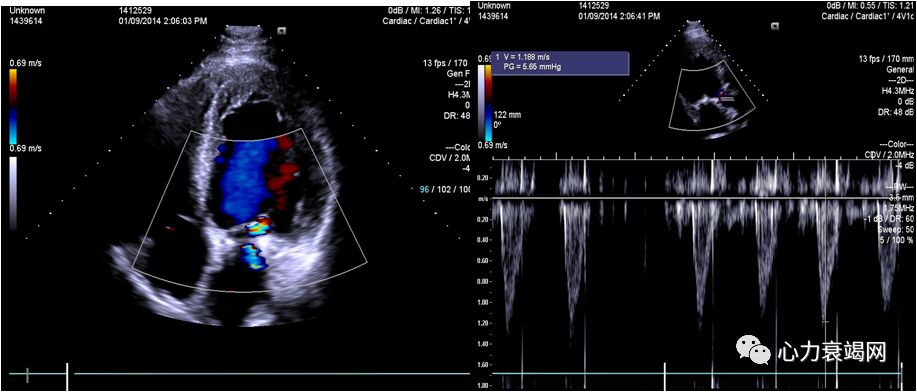

➤ 全心扩大(左房内径48mm,左室内径(d)75mm,(s)62mm)

➤ LVEF36%,肺动脉压80mmHg

➤ 二尖瓣前叶收缩期突向左房,二尖瓣收缩期见中重度关闭不全

➤ 室间隔厚11mm,左室后壁厚11mm